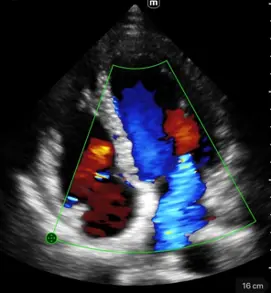

Клинични снимки

Различни режими на визуализация: B-mode, M-mode, Color Doppler, Power Doppler, PW Doppler

B-режим, М-режим, цветен доплер, Power доплер и PW доплер

Множество режими на визуализация